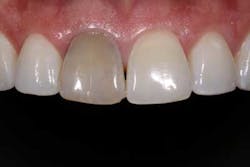

Of all the problems that can occur with implant placement in the anterior, not controlling the zenith of gingival contour may be the most troublesome when it comes to anterior esthetics. Gingival zenith or height of gingival contour is defined as the apex of the gingival height. There are many ways to lose several millimeters of peri-implant mucosa, and it has been shown that even a 1 mm apical displacement of peri-implant mucosa may result in insurmountable limitations in anterior implant esthetics. Things such as deep implant placement, buccal resorption, and relative tooth eruption are just some of the things that can cause this loss of tissue.

Now comes the tricky part — the provisional. Prosthetic control of peri-implant tissue is achieved by properly utilizing your abutment and provisional form. When placing the provisional, it is important to maintain gingival zenith. When fabricating a provisional, my rule of thumb is to create a flat or slightly convex surface facially and lingually, and a concave surface interproximally. This will minimize impingement on the tissue interproximally and, if anything, allow for “overgrown tissue” to develop. This tissue can be easily contoured prior to final placement to give an ideal esthetic gingival architecture.